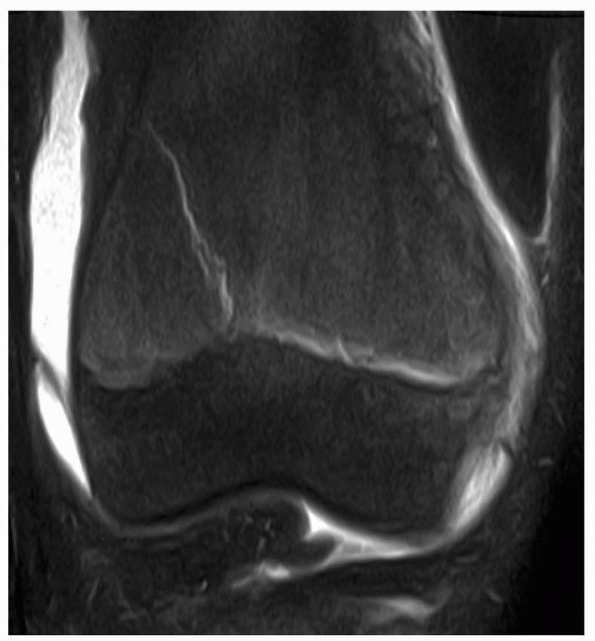

| Figure 5-24 MRI of patient after injury with normal radiographs. MRI clearly documents the presence of a Salter-Harris type II fracture of the distal femur. |

presence of normal plain radiographs (Fig. 5-24). Although the mechanism of injury in type V injuries may be in dispute, in our opinion, the existence of such injuries is not.